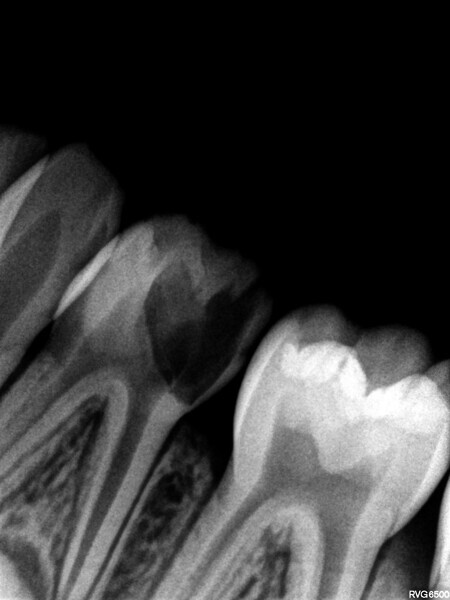

Cas 1 (Figs 1-4)

Cette patiente âgée de 4 ans et 7 mois présentait une douleur qui affectait la seconde molaire temporaire inférieure droite depuis plusieurs jours. L’examen clinique a révélé un gonflement du versant vestibulaire de la gencive et un œdème facial, ainsi qu’une carie occlusale profonde.Un diagnostic de nécrose pulpaire et d’abcès apical symptomatique ayant été posé, un traitement a été prescrit à la patiente, afin de maîtriser l’infection aiguë, et un nouveau rendez-vous a été fixé après l’antibiothérapie. Lors du deuxième rendez-vous, elle ne présentait plus aucune douleur et l’abcès buccal s’était partiellement résorbé. Il a été décidé de procéder à une pulpectomie et à la restauration de la dent. Dans ce cas, la dent présentait une extrusion excessive de matériau d’obturation. Après 15 mois, la réévaluation a confirmé l’absence de signes cliniques ou radiologiques pathologiques, et une apposition osseuse était visible dans la zone de la furcation.